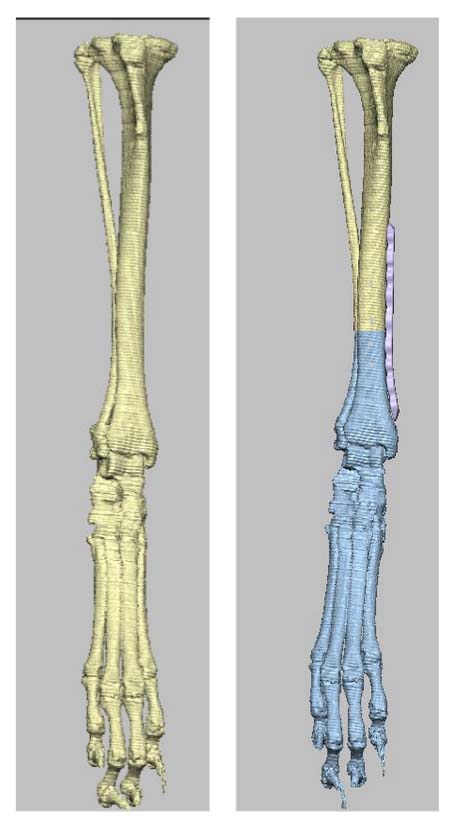

Due to the severe grade 4 right LPL, radiographs were made to assess for an underlying angular limb deformity, which was confirmed.

Further radiographs were not pursued due to the multiplanar (frontal, sagittal, and transverse) limb deformities, as deformities of this significant nature cannot be accurately assessed radiographically using a traditional segmental technique.

Accurate surgical planning for such severe deformities benefit from additional diagnostics, such as cross-sectional imaging, which was recommended and performed.

Pelvic limb computed tomography (CT) scan for computer-aided design (CAD)-based surgical planning was performed readily with sedation.

A method of planning and correction, commonly used in human surgery, has been adapted for the small-animal patient. This method is called the center of rotation of angulation (CORA). With this method, bone axes and joint orientation angles were made to provide guidance for accurate correction of angular limb deformities based on one standard set of geometric principles as they apply to osteotomies, regardless of the bone in question or the type of fixation device.

CT CAD-based approach to deformity planning documented two right femoral deformities:

Excessive anatomical lateral distal femoral angle (aLDFA) = 88.8 degrees

Femoral version 20 degrees

One right tibial deformity (19 degrees of excessive tibial internal torsion)

Correct the right femur angular limb deformities with a mid-diaphyseal oblique closing-wedge ostectomy centered at the CORA of the femoral deformity, which is located within the mid-diaphyseal (do not recommend a traditional distal femoral ostectomy (DFO) as this would result in a significant lateral femoral translation in this specific case). The trochlea is arthritic and hypoplastic, but not overtly deformed. In this case, a traditional block or wedge trochleoplasty is recommended rather than a patellar groove replacement (PGR). In addition, a corrective de-torsional tibial osteotomy has been recommended, as a tibial tuberosity transposition (TTT) is unlikely able to compensate for a torsion of this magnitude.

CT CAD-based surgical plan.